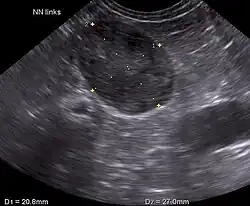

Ultrasonography, CT scans, and MRI are used to identify any abnormality in the pituitary or adrenal gland. This helps diagnose if the patient has pituitary-dependent Cushing's or adrenal-dependent Cushing's.[2]

Blood tests are not always practical for hamsters due to their small size; abdominal ultrasounds can be used to show adrenal gland enlargement.[3]